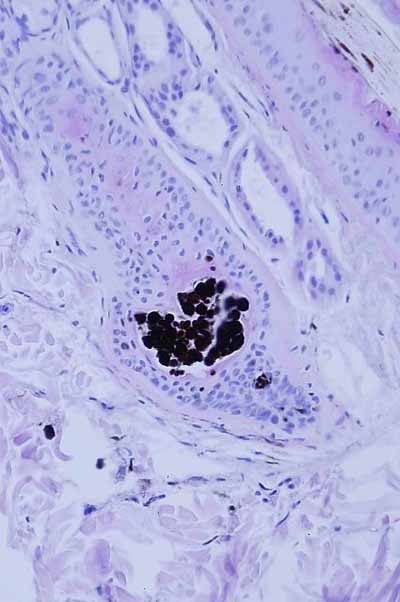

‘’Elles sont avant tout caractérisées par de sévères lésions de pyodermite profonde plus ou moins cicatricielles, stabilisées ou en évolution à type furonculose et d’hydrosadénite rétrograde. On note aussi une dermatose alopéciante avec hyperplasie des structures épithéliales épidermiques et folliculaires, troubles du cycle folliculaire et présence d’anomalies de répartition du pigment mélanique. Présence en outre d’un kyste folliculaire hébergeant des levures du genre malassezia .‘’

Photo 8 DF : anomalie de répartition du pigment mélanique (Photo F. Degorce )